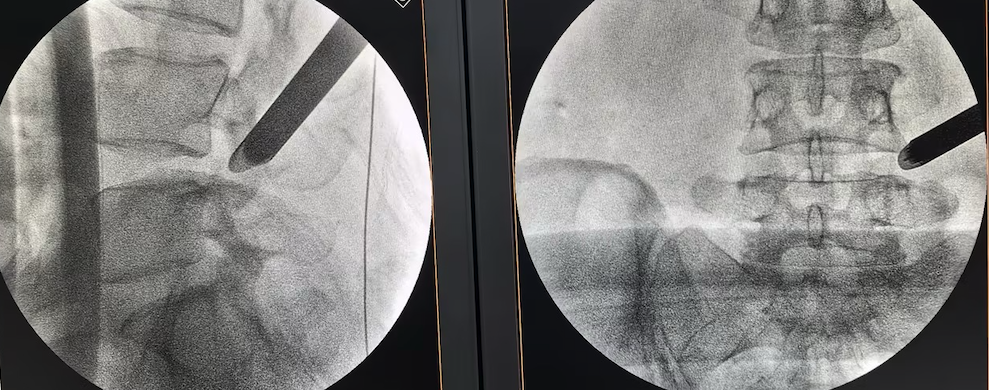

△射频消融技术治疗椎间盘源性腰痛

“我们采用椎间盘射频消融技术,具体来说就是用一根特制的直径只有1mm的细针扎到病变的椎间盘,通上微弱的电流,使病变的椎间盘气化达到减压的作用。”李强主任介绍。术后当天,赵女士就发现困扰多年的腰臀部疼痛消失了,出现喜极而泣的动人场面。她的外籍丈夫特意从国外赶过来致谢:“中国的技术让我们刮目相看。”